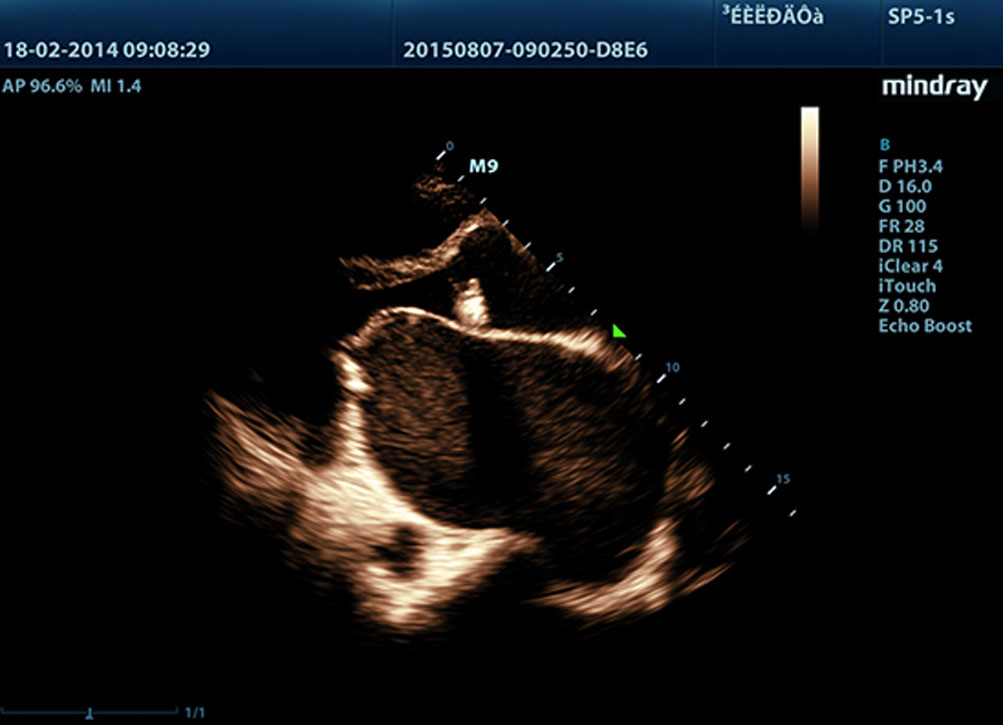

mQuadro, gebaseerd op Mindray's nieuwe generatie echografie platform, zet een geheel nieuwe standaard in echografie. Geavanceerde processoren voor signaaloverdracht en -ontvangst zorgen voor een zeer gevoelige en nauwkeurige echodetectie. Innovatieve transducertechnologie?n zorgen voor een betere penetratie en hogere resolutie voor een sterk verbeterde diagnostische ervaring.

3T Transducer Technology met Single Crystal

Alle M9-compatibele sondes zijn voorzien van MindrayŌĆÖs unieke 3T transducertechnologie wat scherpere beelden oplevert. M9 maakt gebruik van monokristaltechnologie, hetgeen zorgt voor betere penetratie en betere dynamische stroming in kleur, vooral van voordeel bij het scannen van moeilijke pati?nten.

Echo Boost?

MindrayŌĆÖs unieke adaptieve signaalverwerkingstechnologie met intelligente echodetectie gebruikt ruwe signaal-ruis informatie om zwakke echosignalen te verbeteren en onderdrukt omgevingsruis. Dit resulteert in evenwichtigere helderheid en een verbeterde visualisatie van myocardiumweefsellagen.